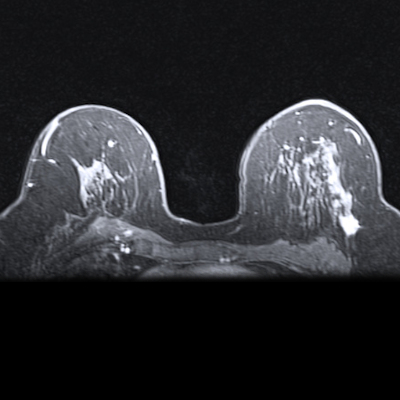

Demonstration of colocalization of pre-existing calcification and incident intraplaque hemorrhage (IPH) in the same plaque. Axial cross sections of the same plaque at the same arterial location on a scan obtained with a T1-weighted gradient-echo noncontrast MRI sequence in a 70-year-old female participant who was free of coronary heart disease and stroke before follow-up MRI. Baseline (left) and follow-up (right) MRI examinations. The blue arrows highlight calcification in a hypointense signal area, while the green arrow indicates IPH as a hyperintense signal. The asterisks mark the lumen of the carotid artery.RSNA